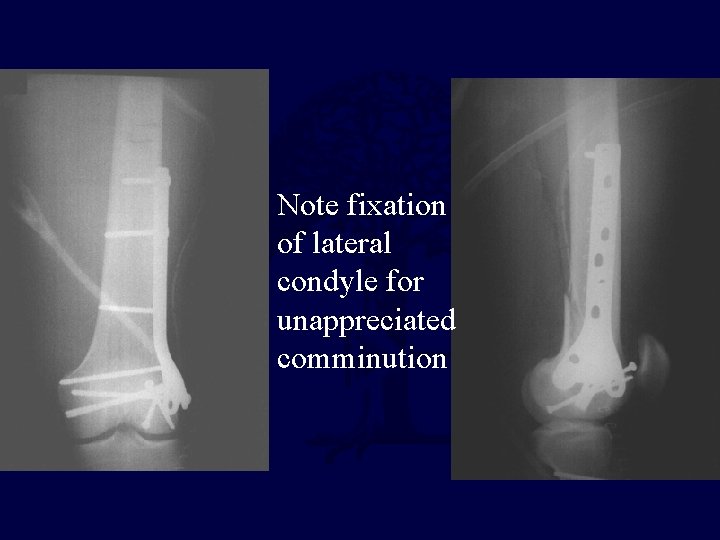

• 23 y. o. male • Single low-energy GSW to leg • ABI > 1. 0 • Neurologically intact • XR: Fracture of distal femur – Moderate comminution noted – Lateral condyle comminuted through articular surface – Not fully appreciated on plain film

Note fixation of lateral condyle for unappreciated comminution